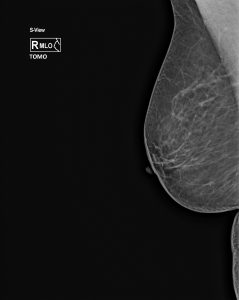

In unserer Praxis werden ausschließlich 3 D Mammographien ( Tomosynthese ) durchgeführt. Unter Tomosythese versteht man eine Schichtuntersuchung der Brust, wobei die vielen Einzelbilder zu einem 3 D Datensatz zusammen gerechnet werden. Dadurch ist eine wesentlich genauere Diagnostik und Früherkennung von Brustkrebs gewährleistet, was auch in entsprechenden wissenschaftlichen Arbeiten belegt ist.

Routinemäßig werden von jeder Brust Aufnahmen in 2 Ebenen angefertigt, bei Bedarf Zusatzaufnahmen. Um eine gute Bildqualität zu erzielen und die Strahlendosis niedrig zu halten, ist es notwendig, die Brust während der Aufnahme zu komprimieren. Dies kann als unangenehm empfunden werden, sollte jedoch nicht schmerzhaft sein. Da die Kompression im allgemeinen während der ersten Zyklushälfte als am wenigsten unangenehm empfunden wird, sollte die Untersuchung nach Möglichkeit entsprechend geplant werden. Der günstigste Zeitpunkt ist der 7. – 14. Tag nach Beginn der letzten Regelblutung.